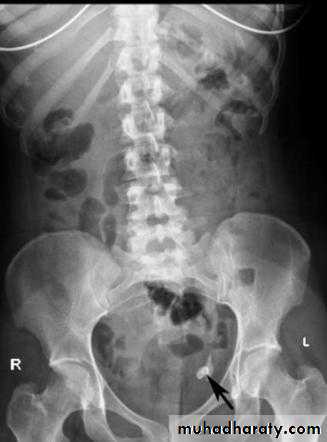

Abdominal calcifications

Assessment of the shape and pattern of abdominal calcification will usually limit the diagnosis to one or two choices. Calcification in the abdomen are likely to be :1. Pelvic vein phleboliths: very common, may be mistaken for urinary stones & fecoliths

12. Faecoliths seen in colonic diverticulae or in the appendix. The presence of appendicolith is a strong indicator of acute appendicitis, often with perforation.